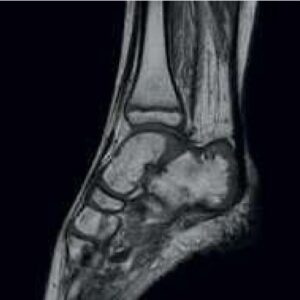

MSK Imaging

The Ortho Suite provides a wide variety of optimized protocols for extremities imaging.